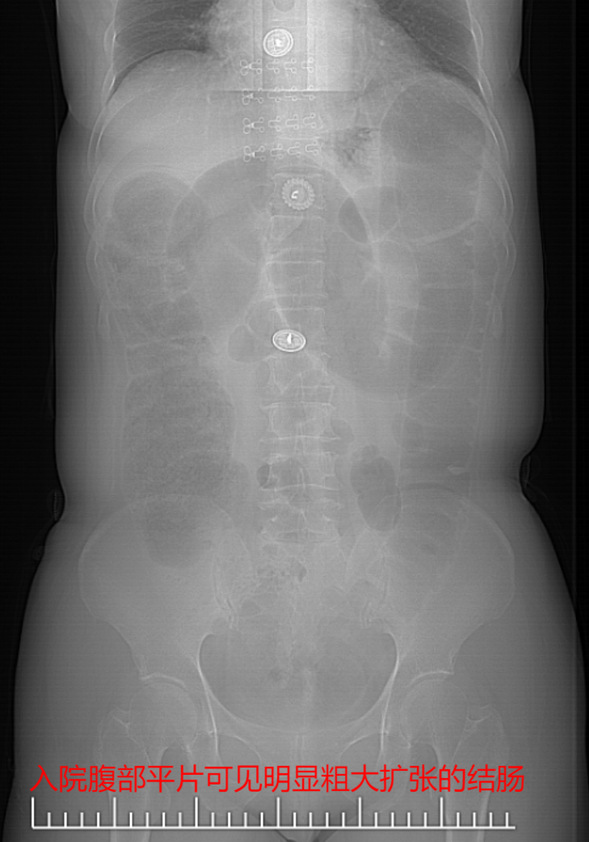

患者于女士,近10天内出现排便困难、排气不畅,近2天内出现进食后呕吐、腹胀、腹痛等症状,在当地医院经灌肠治疗后未见好转,无奈半夜驱车来到我院急诊就诊。全腹CT检查提示,乙状结肠及直肠管壁增厚,结肠梗阻,于是在我院普外科住院治疗。